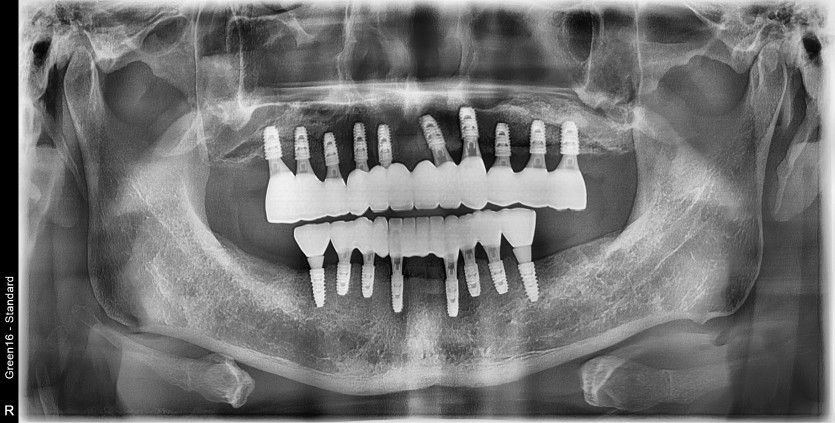

만 58세 전체 임플란트 증례

전체 임플란트 증례입니다.

16개의 임플란트로 완성하였습니다.